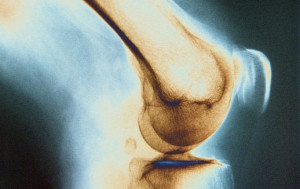

Костный туберкулез поражает позвоночник в более чем 50% случаев, захватывает поясничный, грудно-поясничный и грудной отделы органа.

Рентгенограмма четко указывает на остеопороз и уплощение тел позвонков, сужение межпозвонковых щелей, деформацию. Ранняя диагностика и своевременное лечение помогут не только стабилизировать и повернуть вспять патологический процесс, но и в последствии восстановить или хотя бы улучшить функции органа.